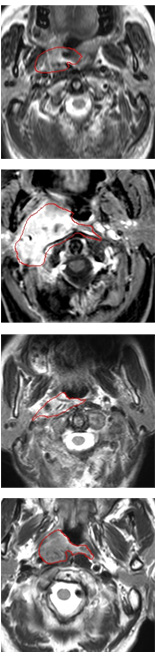

Some examples of spatial attention coefficients are shown in Figure 11. We can see that, several locations may fire at the beginning of training phase and then energy will slowly build up over ROIs and reduce the attention to false positives.